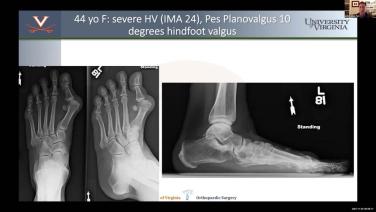

Management of Foot & Ankle Deformities Master Class with Joseph Park, MD - Part 5